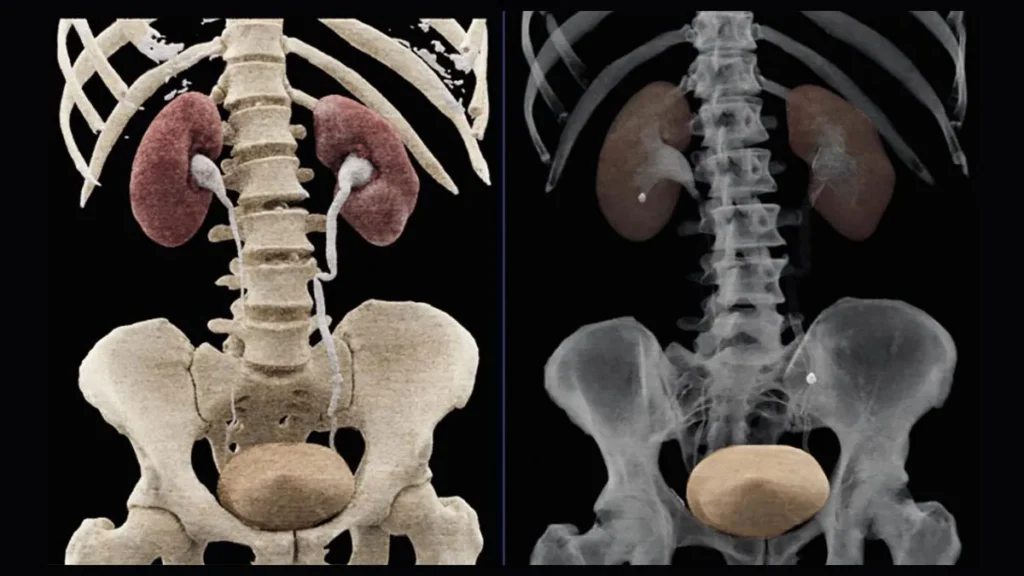

Approach may reduce radiation exposure and costs.